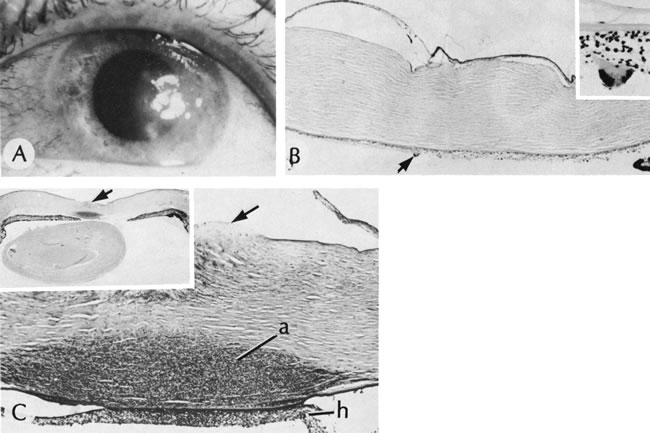

48. Stone D, Kenyon K, Green W et al: Congenital central corneal leukoma

(Peters' anomaly). Am J Ophthalmol 81:173, 1976.

49. Fogle J, Green W, Kenyon K et al: Peripheral Peters anomaly: A histopathologic

case report. Pediatr Ophthalmol Strabismus 15:71, 1978.

50. Heckenlively J, Kielar R: Congenital perforated cornea in Peters'

anomaly. Am J Ophthalmol 88:63, 1979.

51. Varley M, Grossniklaus H, Lass J: Corneal perforation at birth secondary

to Peters' anomaly. Am J Ophthalmol 104:303, 1987.